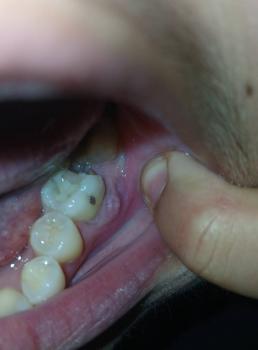

Getting a dental implant after a tooth extraction is one of the most common questions patients ask. The timing depends on your healing, bone condition, and overall oral health.

There are three main options: